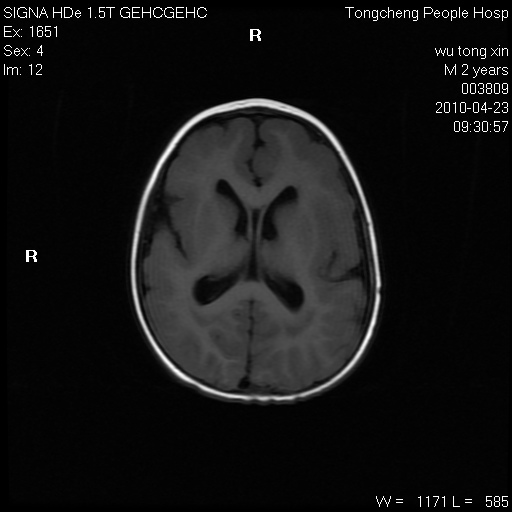

以下是引用赵物学在2010-4-25 12:43:00的发言:[br]巨脑回[br]侧脑室后角低密度影考虑hie或肾上腺脑白质营养不良?[br][br][本贴已被 赵物学 于 2010-4-25 12:51:28 修改过]

以下是引用gaoxiao在2010-4-25 16:54:00的发言:[br]巨脑回畸形。脑白质髓鞘化不良

以下是引用pujunzhi在2010-4-25 21:35:00的发言:[br]考虑 1双侧大脑皮质发育不良 2轻度脑积水 3双侧脑室后角旁片状长t1长t2信号,需继续观察,因为正常小儿此处脑白质的髓鞘化时间可以延迟到4-6岁,才显示正常。